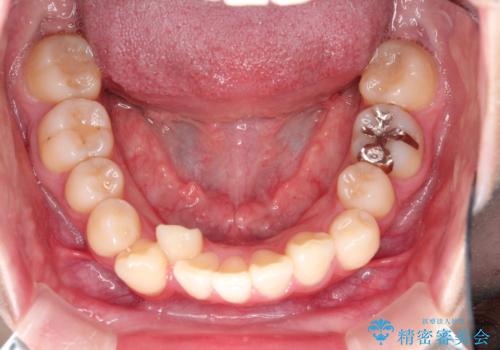

- 上下の前歯に捻れ(捻転)とガタつき(叢生)が見られます。

下の犬歯に関しても捻れと傾き、ガタつきが大きく、歯根の長さも相まって移動の難易度が高くなりがちです。

マウスピース枚数 初回33枚 +追加22枚 +追加31枚

概ね2年で治療完了しました。

マウスピース矯正の特性として動かすのが難しい歯を含むケースでしたが、当院独自の工夫を随所に盛り込み、狙い通りの治療結果が得られました。